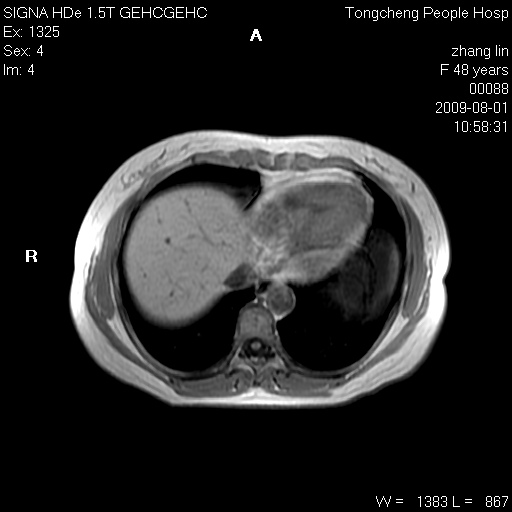

女,48岁。健康体检,彩超发现右肾占位性病变。平素健康。

临床诊断:右肾占位性病变,性质待定(囊肿?肿瘤?)。

上中腹部mr平扫+增强扫描,图像如下:

右肾上极见一类圆形病灶,t1wi呈等信号t2wi呈等高混杂信号,三期增强无强化,边界清---考虑囊肿出血。